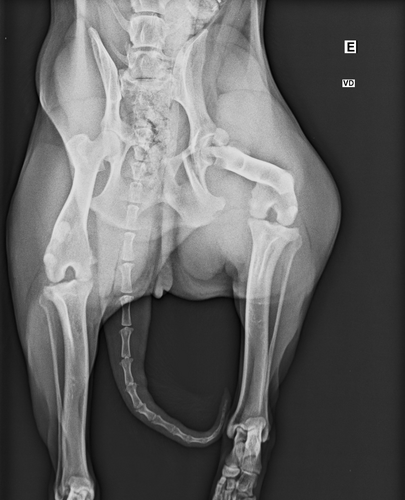

Oi, me chamo Bárbara e estou fazendo essa vaquinha online com um propósito muito especial: ajudar um cachorro de rua, chamado de Nonô, que foi vítima de um atropelamento. Ele acabou sofrendo fraturas graves em uma de suas perninhas.

Nosso objetivo com esta vaquinha online é arrecadar 2.220,00 reais para cobrir os gastos da cirurgia que irá reparar as fraturas na perninha do Nonô. Esse procedimento é crucial para aliviar sua dor, permitir sua locomoção e garantir sua qualidade de vida. Com a sua ajuda, podemos dar ao Nonô uma nova chance de correr, brincar e o melhor: encontrar um lar amoroso.